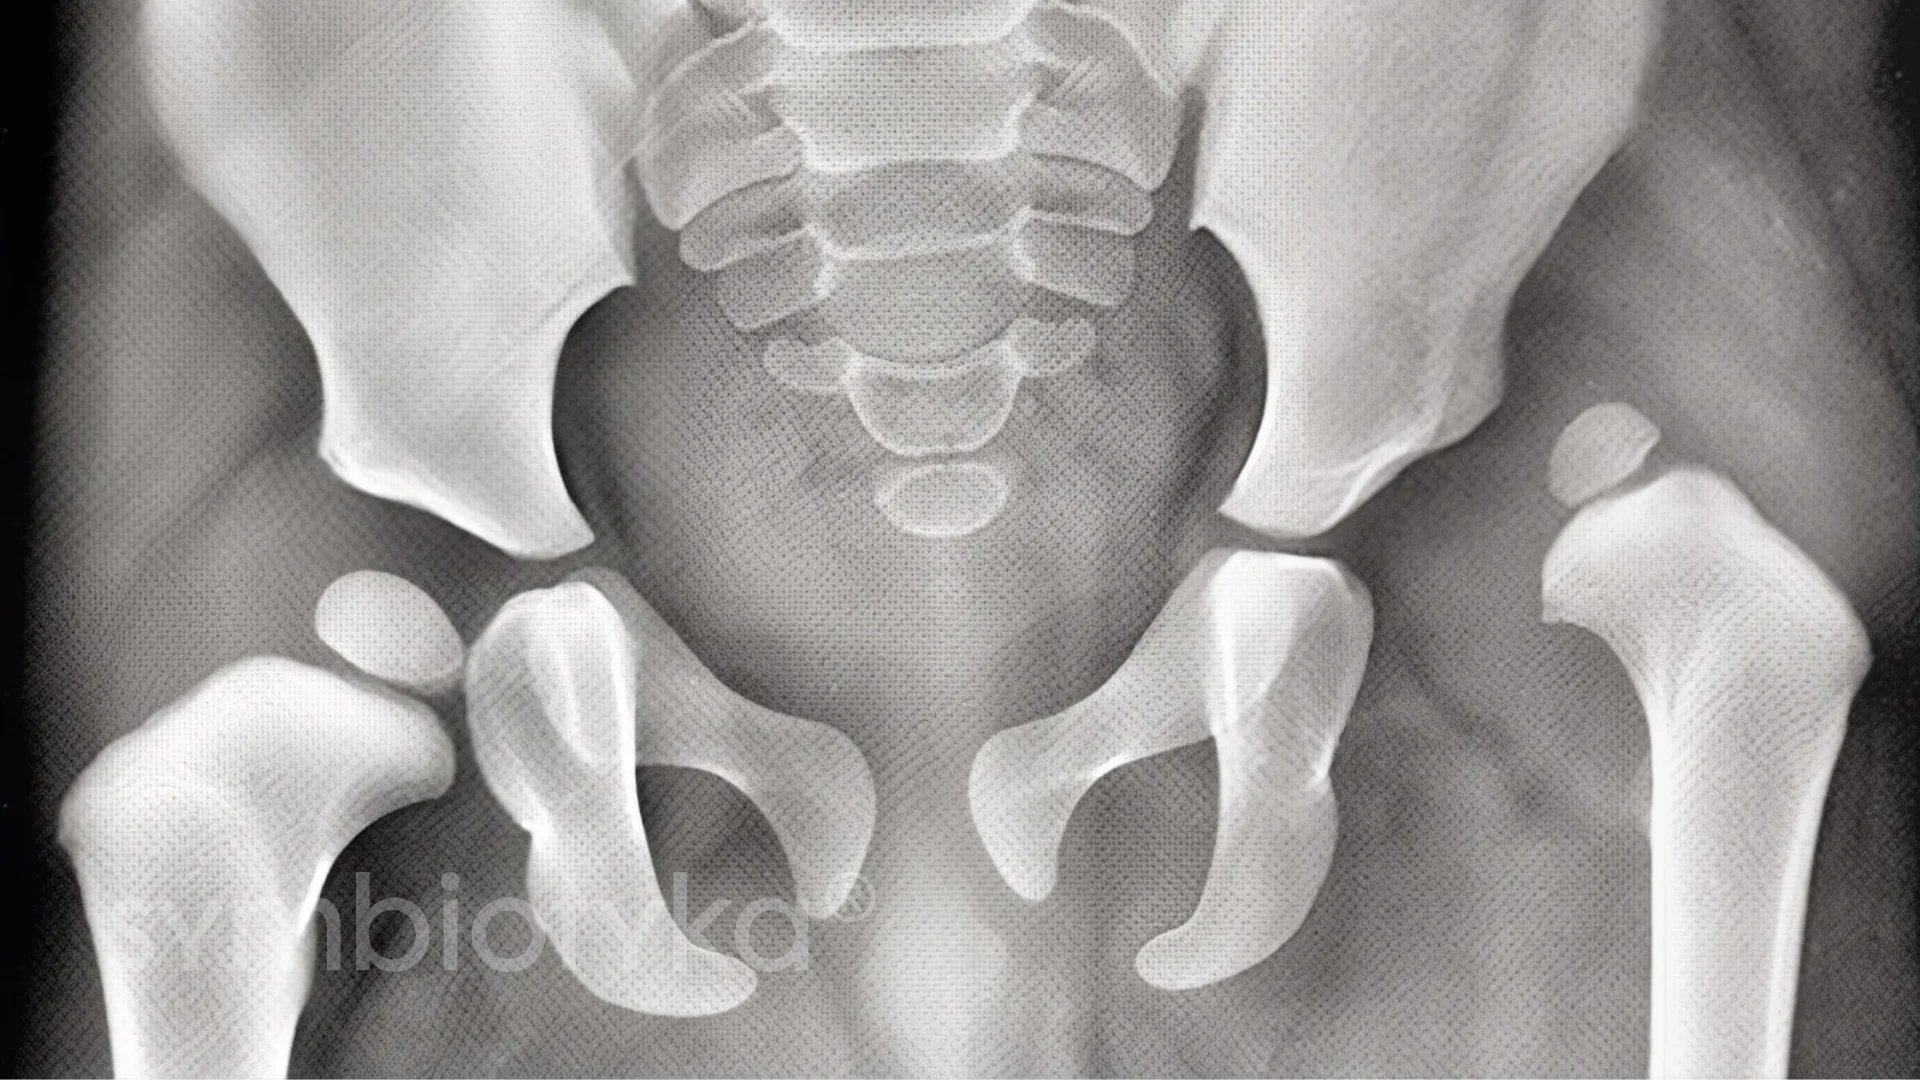

Перед ендопротезуванням пацієнт проходить повне обстеження, щоб виключити ризики та підібрати протез:

Уражена головка стегнової кістки та пошкоджені ділянки кульшової западини тазу видаляються. Якщо є кісткові відростки чи деформації, проводиться їх корекція.

У стегновій кістці формується канал для ніжки імпланта. Поверхня кульшової западини обробляється та готується для точного розташування штучної чаші.